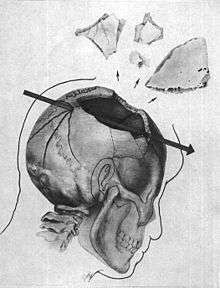

- The wound to the back of the head is described by the Bethesda autopsy as being a laceration measuring 15 by 6 millimetres (0.59 in × 0.24 in), situated to the right and slightly above the external occipital protuberance. In the underlying bone is a corresponding wound through the skull showing beveling (a cone-shaped widening) of the margins of the bone when viewed from the interior of the skull.[8]

- The large, irregularly shaped defect in the right side of the head (chiefly to the parietal bone, but also involving the temporal and occipital bone) is described as being about 13 centimetres (5.1 in) wide at the largest diameter.[8]

- Three fragments of skull bone were received as separate specimens, roughly corresponding to the dimensions of the large defect. In the largest of the fragments is a portion of the perimeter of a roughly circular wound presumably of exit, exhibiting beveling of the exterior of the bone, and measuring about 2.5 to 3.0 centimetres (0.98 to 1.18 in). X-rays revealed minute particles of metal in the bone at this margin.[8]

- Minute fragments of the projectile were found by X-ray along a path from the rear wound to the parietal area defect.[9]

Skull: There are multiple fractures of the bones of the calvarium bilaterally. These fractures extend into the base of the skull and involve the floor of the anterior fossa on the right side as well as the middle fossa in the midline. With respect to the right frontoparietal[10] region of the skull, the traumatic damage is particularly severe with extensive fragmentation of the bony structures from the midline of the frontal bone anteriorly to the vicinity of the posterior margin of the parietal bone behind. Above the fragmentation extends approximately 25 mm. across the midline to involve adjacent portions of the left parietal bone; below, the changes extend into the right temporal bone. Throughout this region, many of the bony pieces have been displaced outward; several pieces are missing. Distributed through the right cerebral hemisphere are numerous small, irregular metallic fragments most of which are less than 1 mm. in maximum dimension. The majority of these fragments lie anteriorly and superiorly. None can be visualized on the left side of the brain and none below a horizontal plane through the floor of the anterior fossa of the skull. On one of the lateral films of the skull (#2), a hole measuring approximately 8 mm. in diameter on the outer surface of the skull and as much as 20 mm. on the internal surface can be seen in profile approximately 100 mm. above the external occipital protuberance. The bone of the lower edge of the hole is depressed. Also there is, embedded in the outer table of the skull close to the lower edge of the hole, a large metallic fragment which on the anteroposterior film (#1) lies 25 mm. to the right of the midline. This fragment as seen in the latter film is round and measures 6.5 mm in diameter immediately adjacent to the hole on the internal surface of the skull, there is localized elevation of the soft tissues. Small fragments of bone lie within portions of these tissues and within the hole itself. These changes are consistent with an entrance wound of the skull produced by a bullet similar to that of exhibit CE 399. The metallic fragments visualized within the right cerebral hemisphere fall into two groups. One group consists of relatively large fragments, more or less randomly distributed. The second group consists of finely divided fragments, distributed in a posteroanterior direction in a region 45 mm. long and 8 mm. wide. As seen on lateral film #2, this formation overlies the position of the coronal suture; its long axis, if extended posteriorly, passes through the above-mentioned hole. It appears to end anteriorly immediately below the badly fragmented frontal and parietal bones just anterior to the region of the coronal suture. The foregoing observations indicate that the decedent's head was struck from behind by a single projectile. It entered the occipital region 25 mm to the right of the midline and 100 mm. above the external occipital protuberance. The projectile fragmented on entering the skull, one major section leaving a trail of fine metallic debris as it passed forward and laterally to explosively fracture the right frontal and parietal bones as it emerged from the head. In addition to the foregoing, it is noteworthy that there is no evidence of projectile fragments in the left cerebral tissues or in the right cerebral hemisphere below a horizontal plane passing through the floor of the anterior fossa of the skull. Also, although the fractures of the calvarium extend to the left of the midline and into the anterior and middle fossa of the skull, no bony defect, such as one created by a projectile either entering or leaving the head, is seen in the calvarium to the left of the midline or in the base of the skull. Hence, it is not reasonable to postulate that a projectile passed through the head in a direction other than that described above. Of further note, when the X-ray films of the skull were presented to The Panel, film #1 had been damaged in two small regions by what appears to be the heat from a spotlight. Also, on film #2, a pair of converging pencil lines had been drawn on the film. Neither of these artifacts interfered with the interpretation of the films.

- The Clark report places the head bullet wound 100 mm (4 inches) above the reported occipital protuberance wound of the Bethesda report. This is important, because it is consistent with a high angle rear entry wound to the skull.